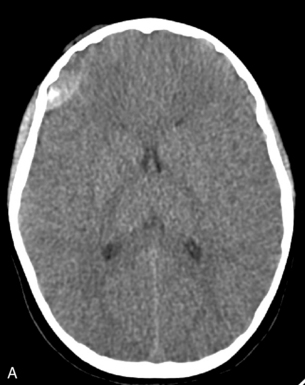

A CT scan will provide important information about the extent and severity of the head injury and potential causes of further deterioration, such as intraparenchymal, subdural, or epidural hemorrhage (Fig. 19-6). In addition, it will provide information about the need for surgical intervention. If a CT scan is performed to evaluate a head injury, the scan should include the upper cervical spine.23 Magnetic resonance imaging (MRI) has been used more often in recent years because it provides better detail of head injuries and may be more useful to predict outcome (see the following discussion under Neck and Spine).24

image image

Fig. 19-6 Epidural hematoma in two CT scans taken 2   hours apart. These two images show the rapid progression of an epidural hematoma. A, This first scan was taken soon after the child’s arrival in the emergency department. The epidural hematoma (blood) is visible as a white density in the patient’s right temporal area (visible on the left side of this image). The lateral ventricles and third ventricles are partially visible as dark densities at the midline and on either side of the midline of this image. B, This second scan was obtained 2   hours later when the child’s level of consciousness deteriorated. The child’s right pupil dilated and reacted sluggishly to light. The image is at the same level as image A and now shows a much larger epidural hematoma (white density on patient’s right side). The lateral ventricles and third ventricle are almost completely obliterated as the result of compression from the expanding epidural hematoma.

This child required urgent surgical intervention. (Images courtesy of Thomas Abramo, Nashville, TN.)